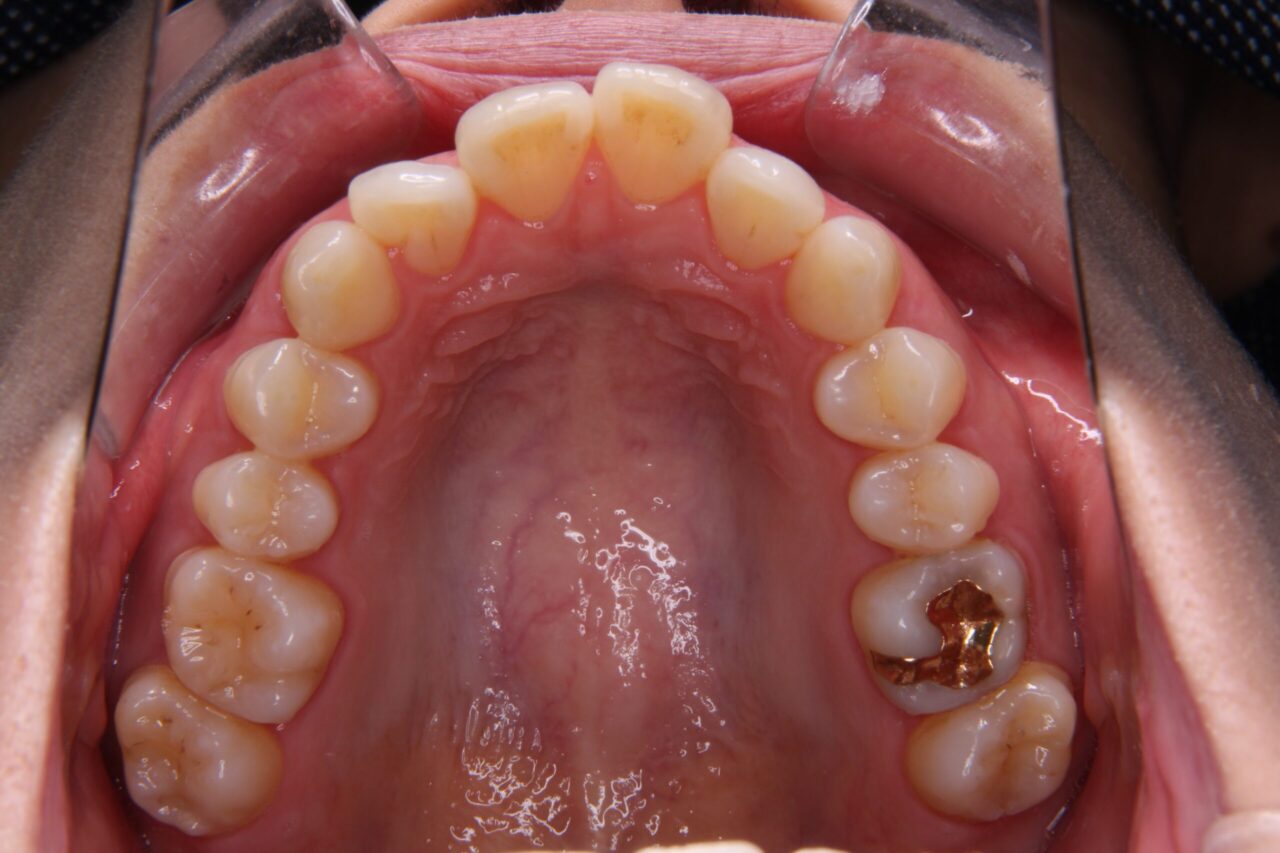

矯正治療前の歯列がこちらです↓↓↓